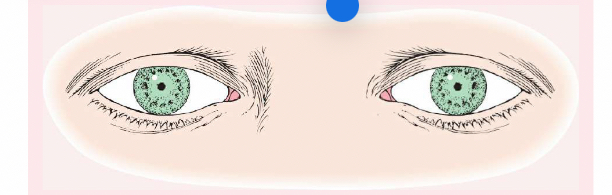

Pseudostrabismus

Normal in young children, the pupils will appear at the inner canthus (due to the epicanthic fold).

Strabismus (or Tropia)

A constant malalignment of the eye axis, is defined according to the direction toward which the eye drifts and may cause amblyopia.

Esotropia

(eye turns inward).

Exotropia

(eye turns outward).

Phoria (Mild Weakness)

Noticeable only with the cover test, is less likely to cause amblyopia than strabismus.

Esophoria

is an inward drift and

exophoria

an outward drift of the eye.